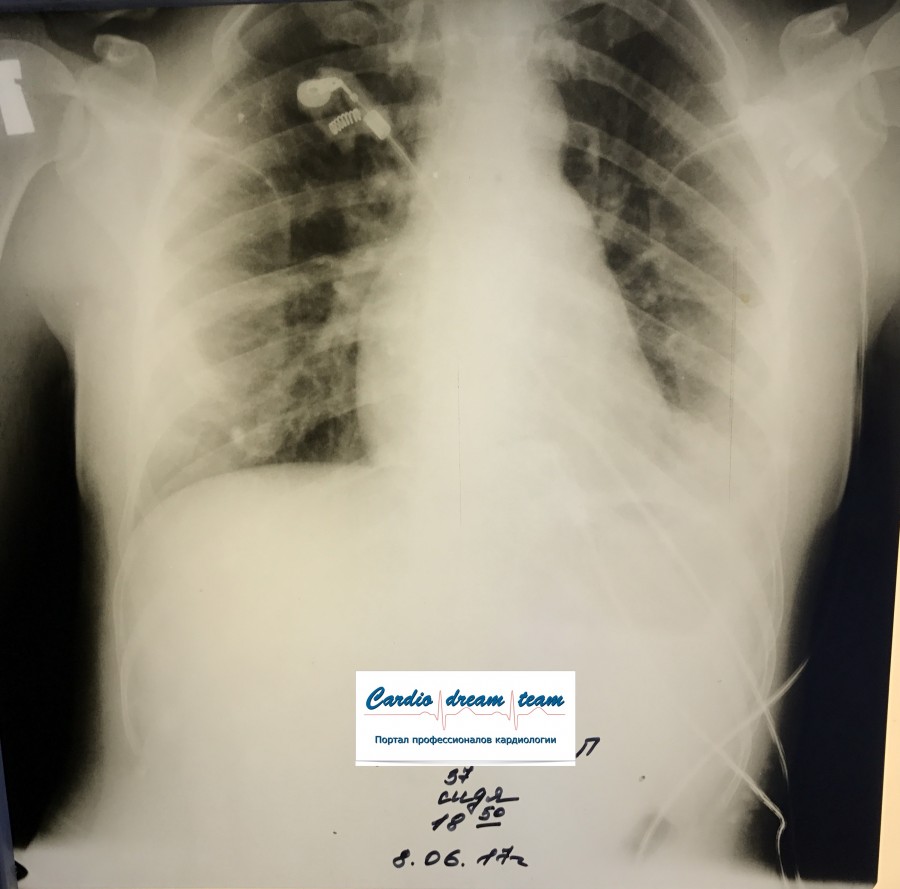

ТЭЛА. Есть увеличение правых отделов сердца. Давность около недели поэтому уже инфаркт пневмония слева с экссудативным плевритом, который виден очень хорошо.

IMG_0931.JPG

IMG_0931.JPG [ 90.74 KiB | Просмотров: 17226 ]